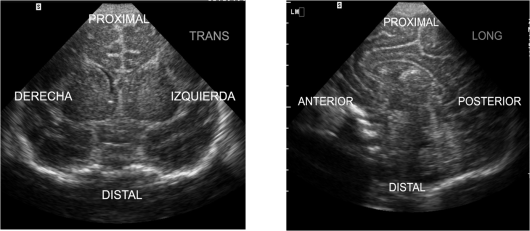

Rotaremos 90º la sonda hacia la derecha del paciente y encontraremos el corte transverso, buscando la parte central de la estructura y su hilio, por donde se nutre el teste, que lo reconocemos por una imagen hiperecogénica y lateral en el Teste.Ese lugar es idóneo para realizar las otras dos medidas mencionadas previamente.

Corte transverso y medidas laterales y antero-posterior.

En esta imagen del testículo, el epidídimo que se ve, isoecogénico sobre el teste derecho, aparecería en la región caudal, pudiendo llevar a error si la sonda estuviese mal posicionada en el corte longitudinal (observa el pictograma).